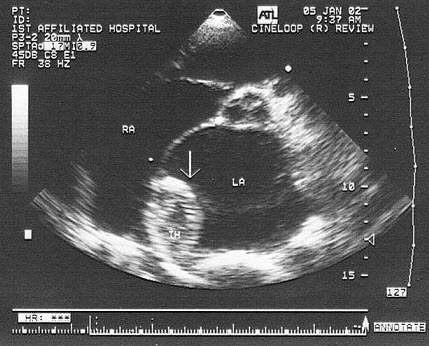

患者有风心病史,该病诊断是()

A.左房黏液瘤

B.左房赘生物

C.左房良性肿瘤

D.左房血栓

E.以上都不是

7、单项选择题

25、单项选择题

该病例最有可能诊断()

B.主动脉瓣关闭不全

C.二尖瓣狭窄

D.二尖瓣关闭不全

E.二尖瓣脱垂

27、单项选择题

A.肺静脉畸形引流

B.上腔静脉型房缺

C.Ⅱ孔型房缺

D.卵圆孔重开

E.下腔静型房缺